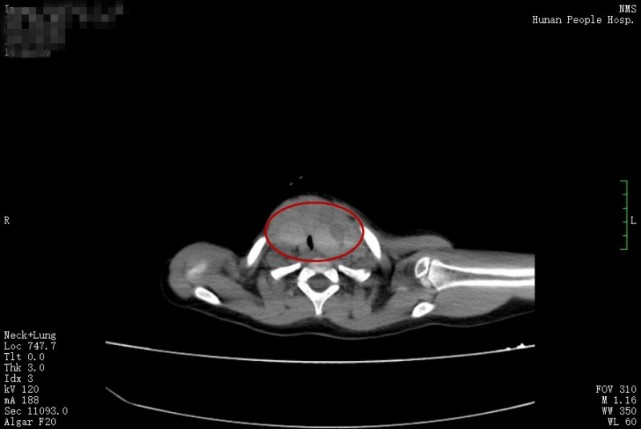

没想到这一年来,小丫脖子上的包块快速长大,特别是近3个月,包块从喉部延伸到了耳后,小丫的呼吸也受到了影响。家人再次带小丫来到张超杰教授的门诊,被收治入院,CT结果显示,小丫的甲状腺肿块已经达到了8×5cm、6×4cm,而她的气管被压迫成了一条缝,最窄的地方只有3mm。考虑到小丫的生命将会受到威胁,张超杰教授为她安排了紧急手术。3月30日,在儿童呼吸科、麻醉科的紧密配合下,张超杰教授团队为小丫进行了甲状腺全切手术,术中病理结果显示为甲状腺乳头状癌。手术十分成功,小丫术后返回普通病房,没有出现明显的术后并发症,4月2日出院回家了。